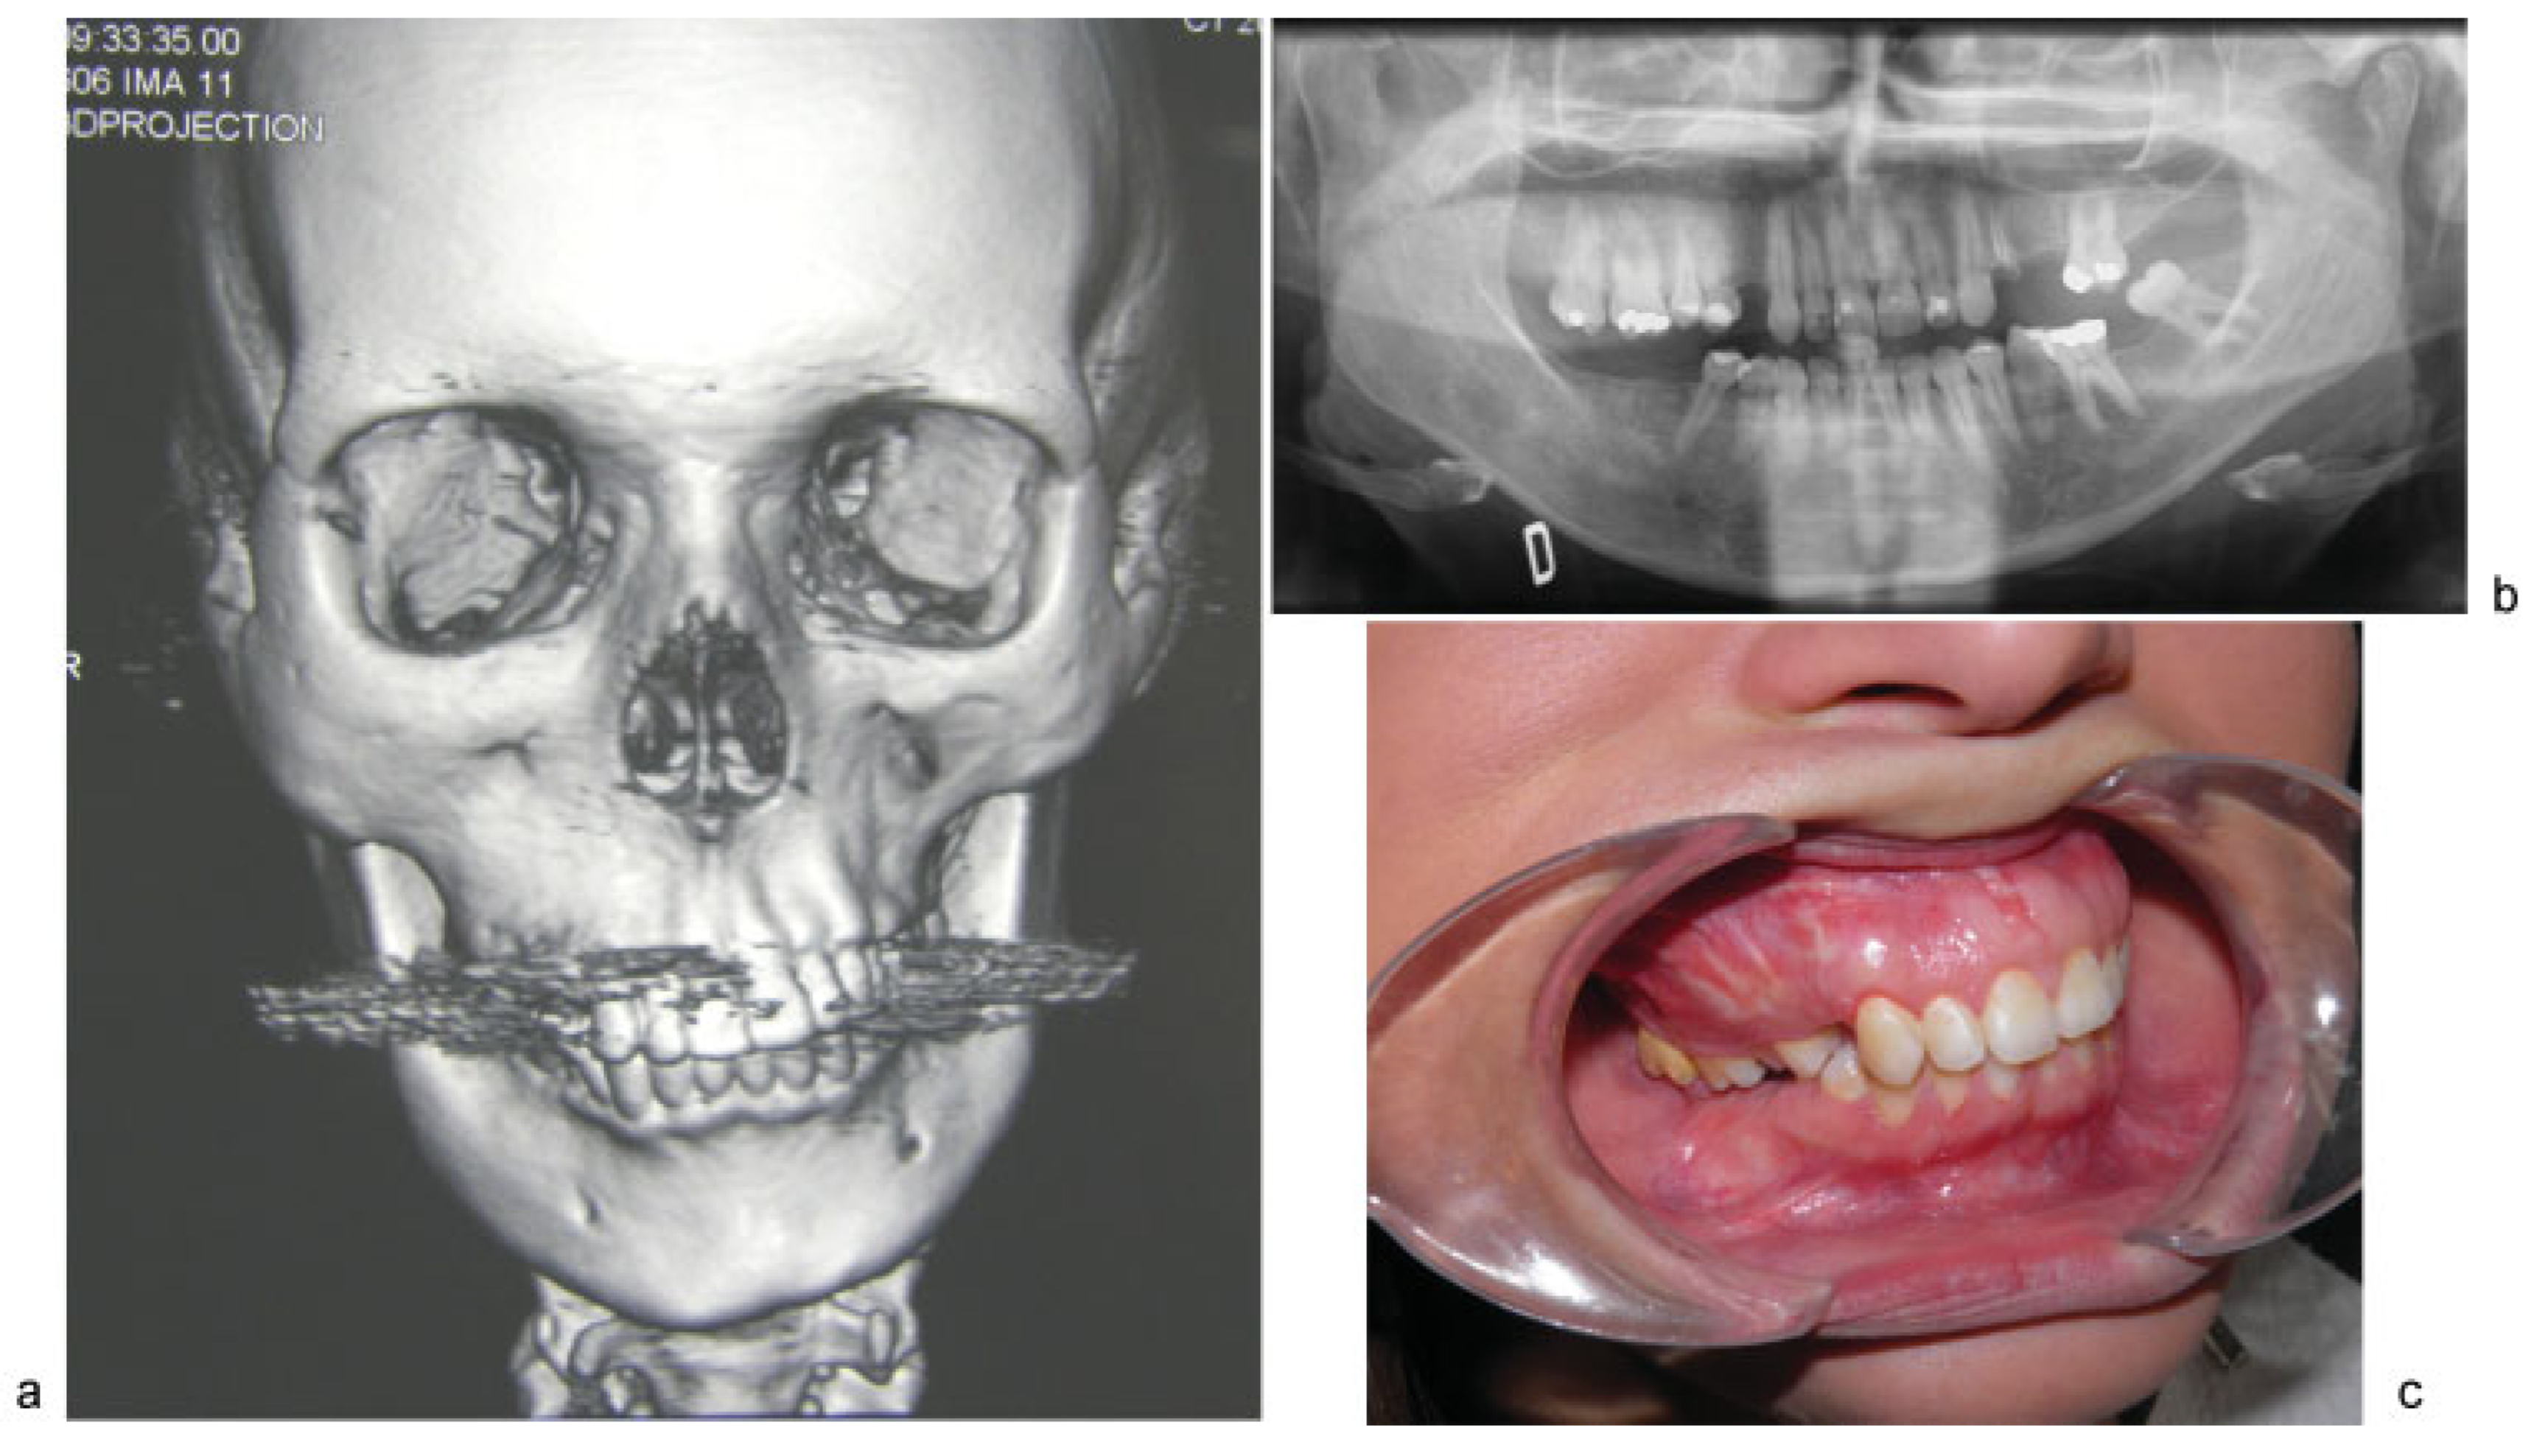

Intraoral inspection showed swelling of all the right maxillary bone from the right vestibular fornix with diastema between the canine and premolars. There was a significant downward prolapse of all the alveolar bone comprising the dental elements 1.4, 1.5, 1.6, and 1.7, with these teeth in contact with the mucosa of the corresponding mandible that appeared edentulous (Figure 1a–c). This caused serious difficulty with chewing and also a lack of space for mandibular prosthetic rehabilitation. The patient was then submitted to segmental osteotomy of the superior maxilla.

Figure 1. (ac) 3D CT scan, OPT X-ray, and intraoral view before surgery.